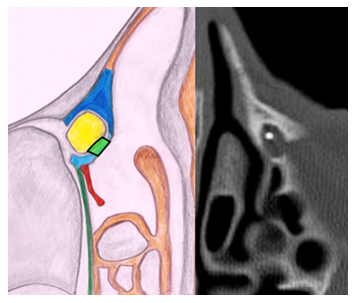

During the surgical procedure the use of a rigid light probe inserted in the inferior lacrimal punctum and canaliculus allows identifying the projection of the lacrimal sac on the lateral nasal wall (Figure 1). In fact, the site of major illumination helps the operator in defining where the bone is thinnest in the lacrimal fossa. This technique further confirms the relation between UP and lacrimal bone, already evaluated with CT. As shown in Figure 2, the prelacrimal UP hides the lacrimal bone making its removal necessary in order to realize the ostomy with the lacrimal sac.

Figure 1 Left nostril – transillumination of the lacrimal sac.

Figure 2 Left nostril – transillumination of the lacrimal sac impeded by pre-lacrimal insertion of UP.